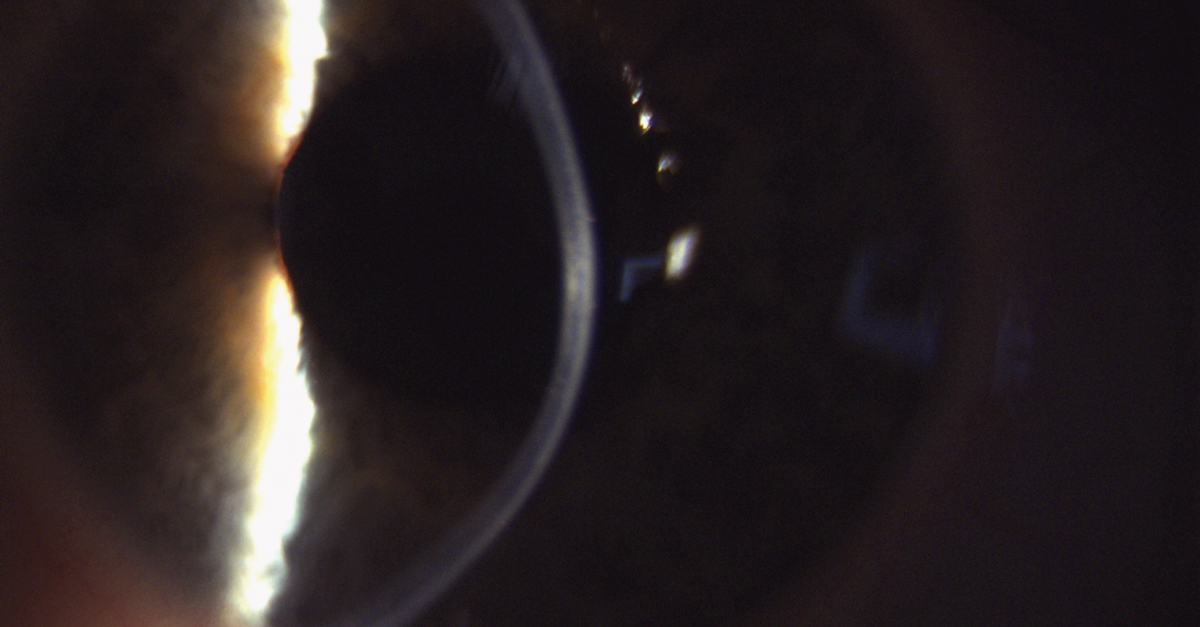

Die ermittelten Werte dienen der Zustandsbeurteilung der KLversorgung und sollen auch Hinweise und Auffälligkeiten aufdecken, die eine Progression des Keratokonus vermuten lassen. Die Beurteilung, ob ein Keratokonus progressiv ist, ist von hoher Bedeutung, da der Patient dann möglicherweise von einer Behandlung mit dem CXL­Verfahren profitieren würde. Eine im  Global Consensus on keratoconus [10] befragte Expertengruppe mit 36 Teilnehmern stellt dazu fest, dass aktuell keine einheitlichen Kriterien und Bewertungsmaßstäbe zur Progressionsanalyse existieren. Die alleinige Messung der Hornhautradien oder Analyse der Hornhauttopographie reicht bei KL tragenden Patienten in der Regel nicht aus, da die Hornhautform nach dem Tragen von KL nicht mit der Form vor der Erstanpassung verglichen werden kann. Durch ungünstige Druckverteilung unter der KL kann es zu einer Epithelverschiebung kommen, die als „corneal warpage“ in der Literatur beschrieben ist. Ob fokale Versteilungen der Hornhautradien dann als Folge einer mechanischen Epithelverschiebung oder als Folge einer Keratokonusprogression auftreten, lässt sich durch eine Kombination aus Topographie und Pachymetrie feststellen. [11] Auch bei durch KL unbelasteten Augen kann die Verdünnung des Hornhautstromas durch eine Zunahme der Epitheldicke kompensiert werden, sodass die Messung der Hornhautradien in diesen Fällen nicht aussagekräftig ist. Abbildung 3 zeigt die spaltlampenmikroskopische Aufnahme einer Hornhaut mit Keratokonus und stromalen Narben. Abbildung 4 zeigt die OCT­Aufnahme derselben Hornhaut wobei die Aufhebung der Strukturen und Schichtgrenzen sowie die Epithelverdickung in Bereichen mit starker stromaler Verdünnung gut zu erkennen sind.

Keratokonushornhaut